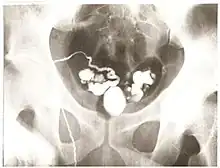

Vasography is an X-ray study of the vas deferens to see if there is blockage, oftentimes in the context of male infertility.[1] An incision is made in the scrotum, contrast is injected in the vas deferens, and X-rays are taken from different angles.[1] Thus, it is an invasive procedure and carries risk of iatrogenic scarring and obstruction of the vas.[2] Vasography has traditionally been considered the gold standard imaging modality for evaluating the seminal tract patency.[3]

To avoid performing an extra operation, vasography is encouraged to be done at the time of correction of the obstruction, and thus should not be done as an isolated outpatient procedure.[2]